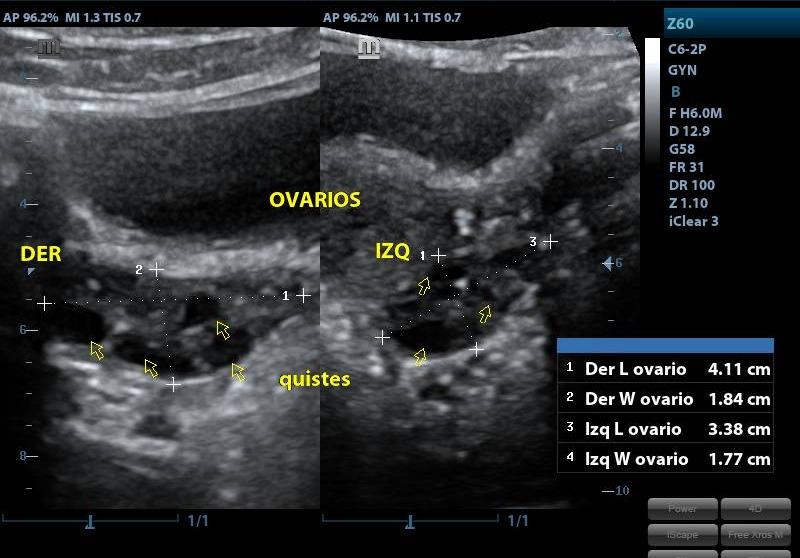

ECOGRAFIA ENDOVAGINAL

CONDICIÓNNO REQUIERE PREPARACION PREVIA

TIEMPO20 MINUTOS

TIPO RESULTADOSIMAGENES ECOGRAFICAS

ESPECIFICACIONESSE ESTUDIA: UTERO ANEXOS OVARIOS IMPLANTACION SACO GESTACIONAL VESICULA VITELINA LONGITUD DE EMBRION (LCC) PRESENCIA DE LATIDOS CARDIACOS OBSERVACION REACCION CORIODECIDUAL, DESCARTAR: HEMATOMAS. MIOMAS QUISTES TUMARACION